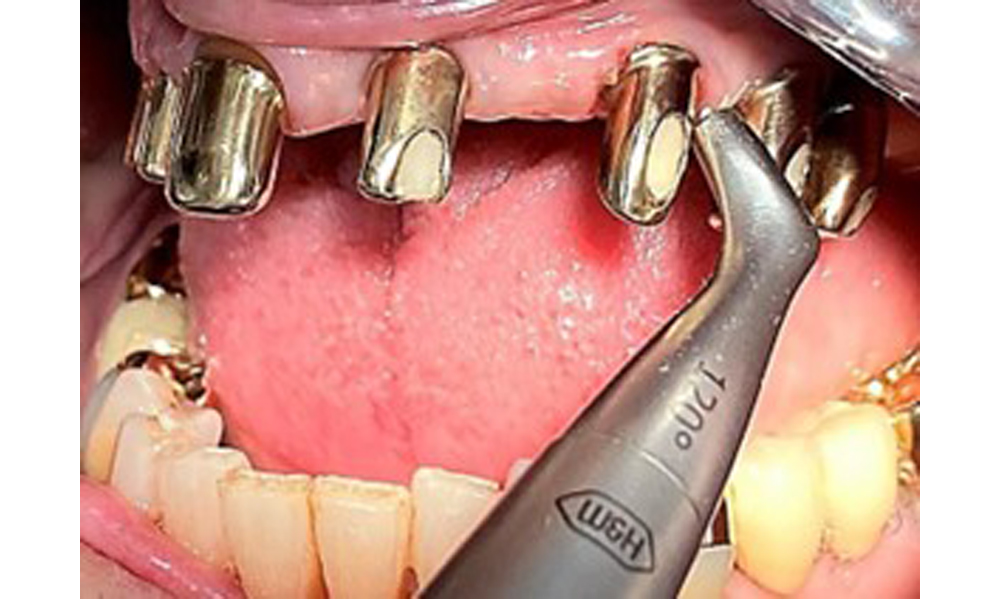

Occlusal view: Maxilla with removable, palateless denture.

Fig. 3: Occlusal view: Maxilla with removable, palateless denture.

The patient was fitted with a combined removable maxillary telescopic prosthesis more than 25 years ago (Fig. 1, Fig. 2, Fig. 3) and is very happy with her dentures. The patient has an adequate fixed denture for the mandible (Fig. 4).

The dental findings are as follows: Combined removable implant and tooth-supported telescopic prostheses on implants 15, 13, 21, 23, 24, 25 and tooth 11 (Fig. 1, Fig. 2, Fig. 3). The patient was fitted with a fixed mandibular denture. Adequate bridges were present over 37 to 34 and 45 to 47 (Fig. 4), the crown margins were intact and there were no active caries. A composite filling with a marginal gap was present on tooth 43. There was mandibular gingival recession, exposing 1 to 3 mm of root surface. This also applies to 11.